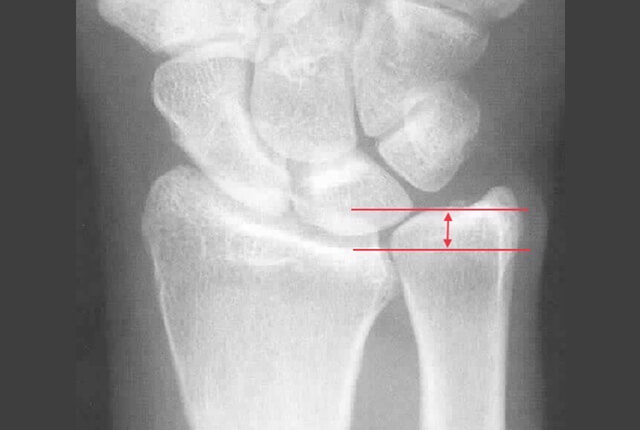

• 単純X線でplus variance

• 単純X線でDRUJの開大

単純X線でDRUJの開大